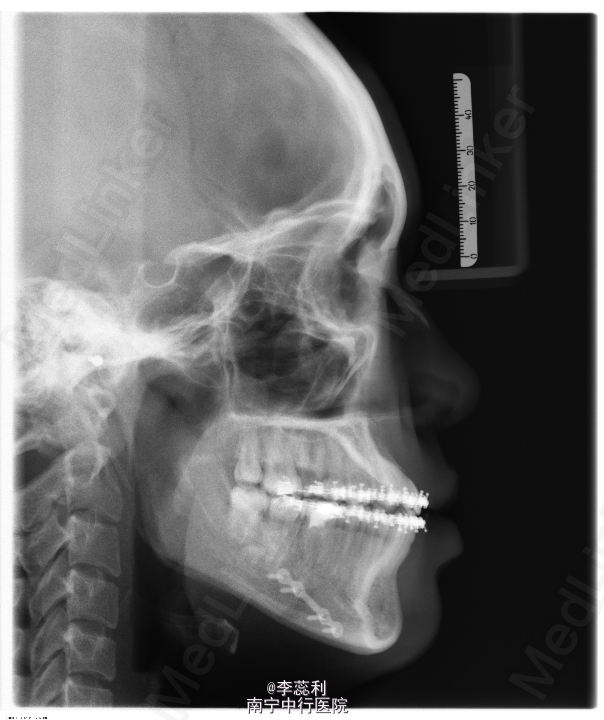

青年女患者,正颌术后1年,要求拆除钛板,患者于1年前因下颌偏颌畸形入院,于2014年6月18日行“左侧下颌升支矢状劈开后退术+去骨皮质术+骨内坚固内固定术”

双侧颌面部基本对称,双侧颞下颌关节动度正常,无疼痛及弹响,双侧颞下颌关节区无明显压痛,开口型“↓”,开口度5.9cm。口内检查:左下下颌前庭沟见手术瘢痕,上颌牙列正畸托槽固定在位,下颌正畸托槽拆除,前牙浅覆合浅覆盖,下颌中线偏右2mm,双侧后牙咬合关系尚可。全景片示左下颌骨固定钛板位于35,36,37根尖方向